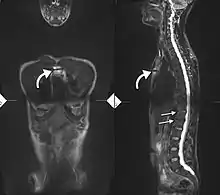

Lateral X-ray of the mid back in ankylosing spondylitis

Lateral X-ray of the neck in ankylosing spondylitis

X-ray showing bamboo spine in a person with ankylosing spondylitis

CT scan showing bamboo spine in ankylosing spondylitis

T1-weighted MRI with fat suppression after administration of gadolinium contrast showing sacroiliitis in a person with ankylosing spondylitis